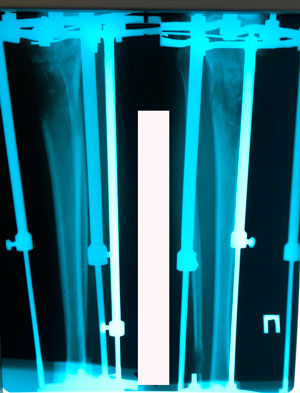

Исходник - 24 года.

Диагноз: врождённое укорочение правой голени на 4 см.

Дата операции - 10.07.2019г.

Костный регенерат в динамике, в процессе удлинения.